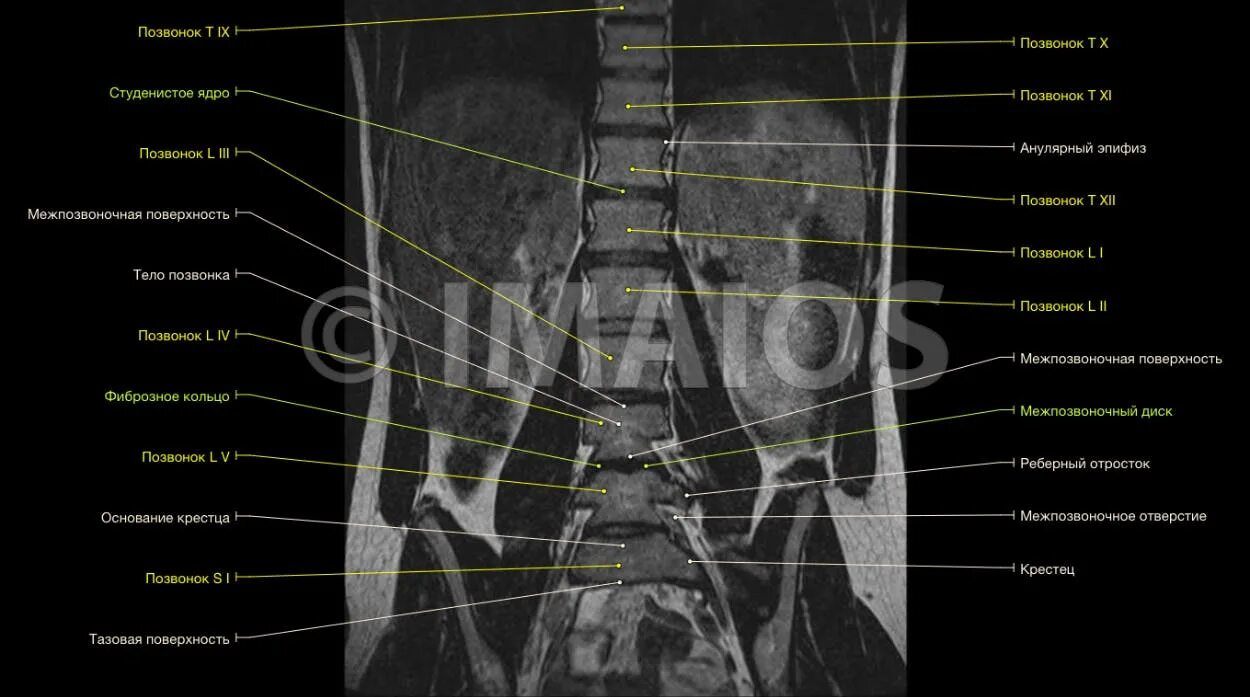

Как делают кт пояснично крестцового отдела